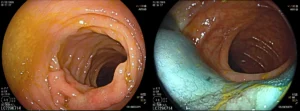

Με επιτυχία διεξήχθησαν δύο περιπτώσεις ασθενών: αφαίρεση μεγάλου πολύποδα παχέος εντέρου και μεγάλου επίπεδου πολύποδα δωδεκαδακτύλου με την τεχνική της ενδοσκοπικής βλεννογονεκτομής (Endoscopic Mucosal Resection – EMR) σε ιδιαίτερα δύσκολη θέσεις.

Η μέθοδος EMR είναι μια προηγμένη θεραπευτική ενδοσκοπική τεχνική για την αφαίρεση μεγάλων πολυπόδων. Χρησιμοποιείται κυρίως για την αφαίρεση επιφανειακών ή μεγάλων πολυπόδων (συνήθως >2cm) στο παχύ έντερο ή το στομάχι, που δεν μπορούν να αφαιρεθούν με την κλασική πολυποδεκτομή.

Στη διαδικασία αυτή, εγχέεται κάτω από τον πολύποδα φυσιολογικός ορός (συχνά μαζί με αιμοστατικά φάρμακα ή ειδική χρωστική) χρησιμοποιώντας έναν λεπτό καθετήρα. Αυτό ανασηκώνει τον πολύποδα, δημιουργώντας ένα «μαξιλάρι» προστασίας για τα βαθύτερα στρώματα του εντέρου.

Στη συνέχεια, ο γιατρός παγιδεύει τον πολύποδα με έναν ειδικό βρόγχο και τον αφαιρεί, είτε με τη χρήση ηλεκτρικού ρεύματος (hot EMR) είτε χωρίς (cold EMR), στέλνοντάς τον για βιοψία. Τέλος, αν κριθεί απαραίτητο λόγω του μεγέθους ή της θέσης της τομής, τοποθετούνται μεταλλικά κλιπ για να κλείσει η πληγή και να αποφευχθούν μελλοντικές επιπλοκές.